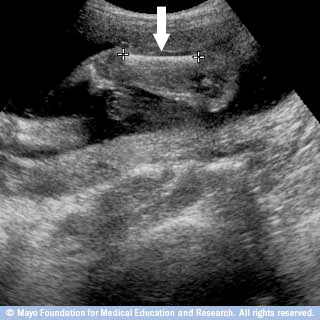

منطقة الحبل السري لدى الجنين

هنا يشير السهم إلى المنطقة التي يتصل فيها حبل السرة مع بطن الجنين.

بواسطة فحص هذه المنطقة قد يكون بإمكان طبيبك استبعاد أو تشخيص حالات مثل بروز المحتويات البطنية عبر فتحة في السرة (القيلة السرية) وخلل أو انفصال في النسيج الذي يُغطي حائط البطن (انشقاق البطن الخلقي).